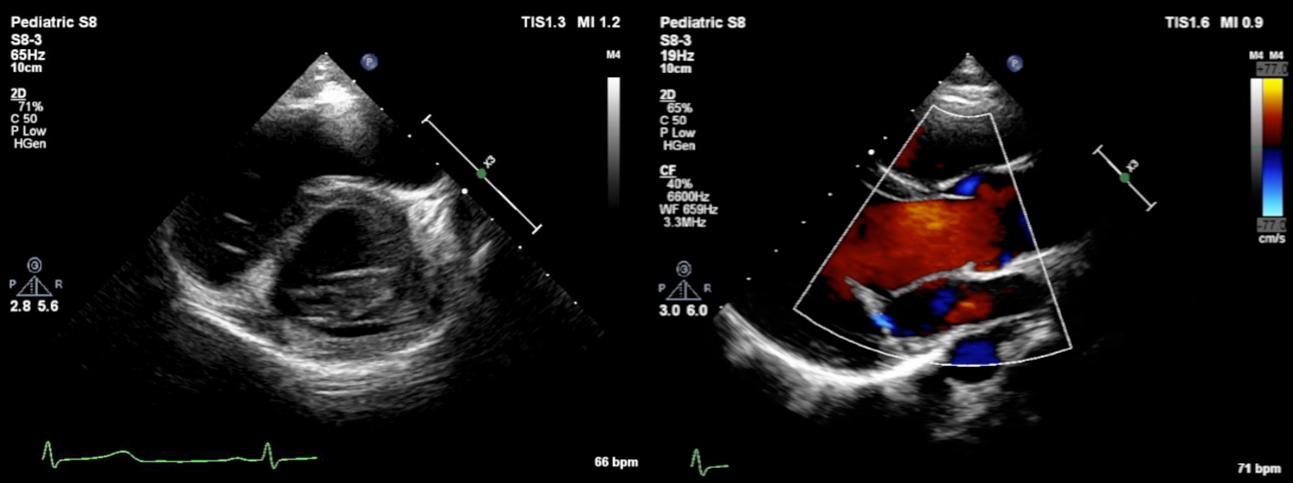

術後18日の心臓超音波検査では,MRはmildであった.術後9年6か月時,MRはtrivialで,また,僧帽弁位の最大流速(Vmax)は0.9 m/sであった.自己心膜を含めた後尖の可動性は低下しているものの,自己心膜の肥厚は軽度で,石灰化は認めていない(Fig. 4).

Pediatric Cardiology and Cardiac Surgery 35(1): 52-58 (2019)

Fig. 4 Postoperative echocardiogram (9 years and 6 months) of case 1

The augmented autologous pericardium is mildly thickened and its movement is reduced. Mitral valve regurgitation is still trivial.